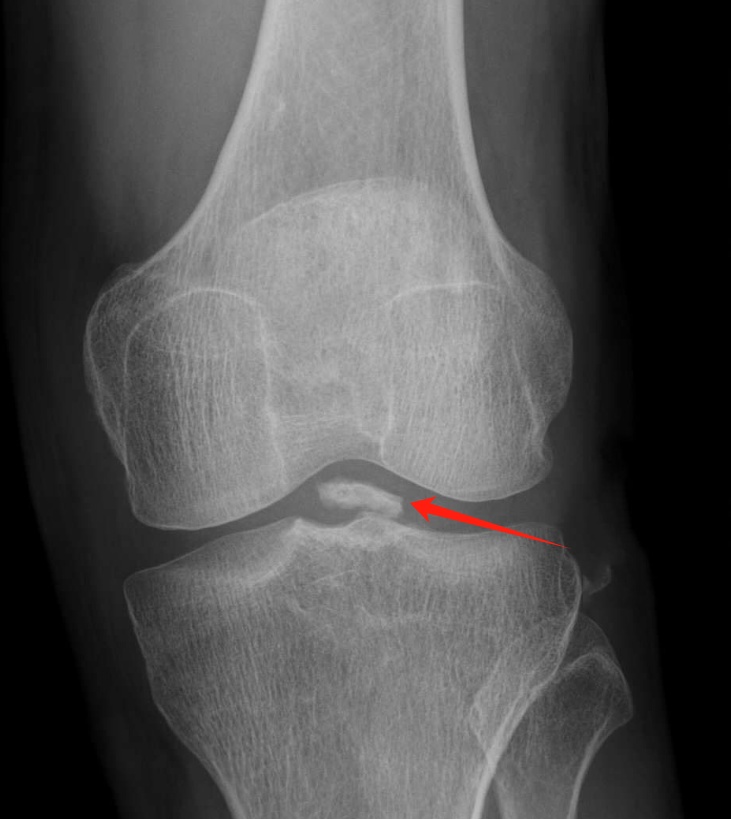

74岁的老杨,因为左膝的肿胀、疼痛及行走困难来到我们医院求治。询问病史患者有外伤史,进一步X光和MRI检查发现他的膝关节存在退行性变和软骨磨损,程千副主任是患者的主诊医师,通过对老杨病史的详细询问及影像学检查的分析,他判断引起患者膝关节疼痛及行走不稳的原因是——膝关节游离体。这些小小的关节内松散碎片,常常是因为外伤或关节退变而形成。它们在关节内自由移动,时而卡在关节之间,导致剧烈疼痛和行动不便。

程千副主任采用结合现代技术的治疗方案——单髁表面置换术配合关节镜对这些游离体进行清除。通过关节镜技术,精准定位并成功清除了18个游离体。随后,进行了单髁表面置换术,有效替换了受损的关节表面。高精度和微创的治疗方法不仅缩短了恢复时间,还显著提高了手术的成功率。

术前

术后

随着年龄的增长以及不当运动造成的损伤,膝关节里会出现一些不速之客,它们就像是膝盖里的“小石头”,这就是膝关节游离体。是从关节软骨或骨头上脱落下来的碎片。大小不一,从几毫米到几厘米都有。这些游离体可以在关节内自由移动,犹如“老鼠”一般,因此又被称为关节鼠。